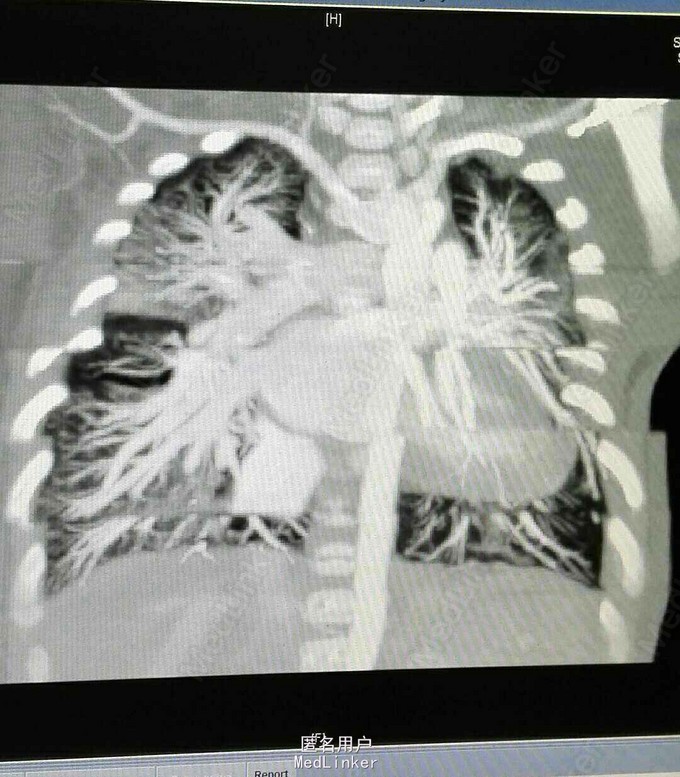

查体 生命体征平稳,双肺呼吸音清,未闻及干湿性罗音,心率规整,于胸骨左缘第二肋间可闻及3/6期收缩期杂音,腹部平软无压痛反跳痛,双下肢无水肿。 辅助检查 心脏彩超示 先天性心脏病 右肺动脉起源于主动脉 动脉导管未闭 三尖瓣反流 肺动脉高压。 心脏CT 先天性心脏病 右肺动脉起源于主动脉 动脉导管未闭 肺动脉高压

侧肺动脉起源于主动脉是一种极为罕见的先天性心脏病,有报道其发病率仅占同期住院先心病例的0.05%其中右肺动脉起源异常较左肺动脉起源异常多见。本病多合并有其它血管畸形如动脉导管未闭,室间隔缺损、法洛四联症等。由于患侧肺持续接受升主动脉的高压灌注,可较早出现肺动脉高压及肺血管的相应改变,健测肺不仅接受肺动脉的双倍血流量灌注,还接受合并的畸形如动脉导管未闭的分流灌注因而亦可能早期就出现体循环压力相似的肺动脉高压及肺小血管改变。故本病唯一有效的治疗方法是外科手术,且一经确诊就应尽快手术,根治手术的主要禁忌症是双侧肺血管的阻塞性病变而非肺动脉高压和肺血管阻力的升高。术中应充分游离异常起源的肺动脉并在转流前同未闭的动脉导管一道予以阻断,防止发生灌注肺。